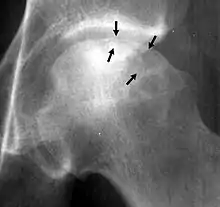

Crescent sign

In radiology, the crescent sign is a finding on conventional radiographs that is associated with avascular necrosis.[1][2][3] It usually occurs later in the disease, in stage III of the four-stage Ficat classification system.[1] It appears as a curved subchondral radiolucent line that is often found on the proximal femoral or humeral head.[1] Usually, this sign indicates a high likelihood of collapse of the affected bone.[1] The crescent sign may be best seen in an abducted (frog-legged) position.[1][4]

The crescent sign is caused by the necrotic and repair processes that occur during avascular necrosis.[1][2] Osteosclerosis occurs at a margin where new bone is placed over dead trabeculae.[1] When the trabeculae experience stress leading to microfractures and collapse, the crescent sign appears.[1]